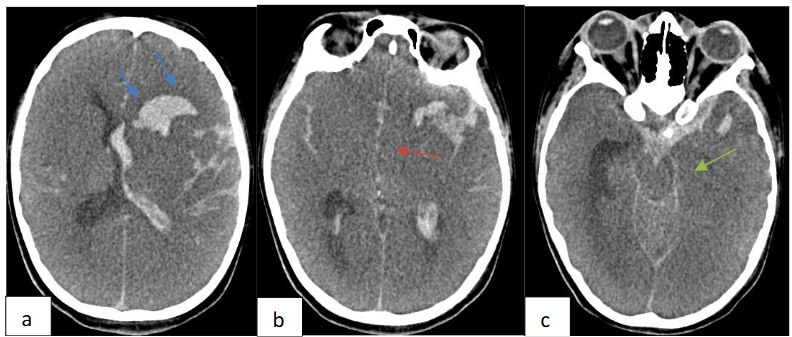

The diagnosis of IE complicating HCM was retained on the basis of ultrasonographic arguments encompassing a valvular vegetation with new onset of mitral regurgitation associated with fever. A thoraco abdomino pelvic and plain brain computed tomography scan were performed to assess the extent of the infection and were initially negative. The patient was managed with intra venous antibiotics: ampicillin, oxacillin and gentamycin and was operated three days after his admission. He underwent a mitral valve replacement and septal myomectomy. The evolution was marked by clinical status improvement with apyrexia, regression of the biological inflammatory syndrome and disappearance of the sub-aortic gradient and mitral regurgitation. On day 7 of hospitalization, the patient suddenly developed convulsions. An urgent non contrast brain computed tomography revealed left frontal intra axial hematoma with intra ventricular and subarachnoid hemorrhage along with diffuse brain edema, subfalcine and left uncal herniation as shown in Figure 6.

Brain CT angiography demonstrated left middle cerebral artery distal M1 segment saccular aneurysm formation with irregular and lobulated contours as shown in Figure 7.